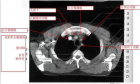

详尽的胸部CT影像示意图

胸部的CT是通过X线计算机体层摄影(CT)对胸部进行检查的一种方法。正常胸部CT层面较多,每一层面结构所表现的图像不同。下面是胸部CT图文示意图,可帮助临床医生详细了解CT结构。我们一起来看一下吧。Re ... [